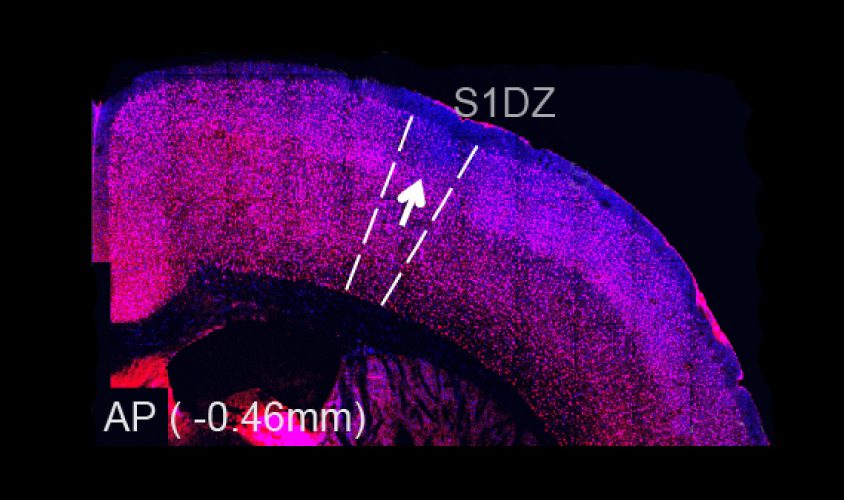

The patches are found specifically in the cerebral cortex, the brain’s outer layer. They consist of atypical clusters of cells and disrupted brain architecture.

The researchers also examined the pups’ brains for neurons that contain parvalbumin. This protein is a marker for a class of neurons that inhibit brain activity. Parvalbumin typically shows up throughout a specific layer of the cortex. But the brains of these pups contain patches of neurons that lack the marker.